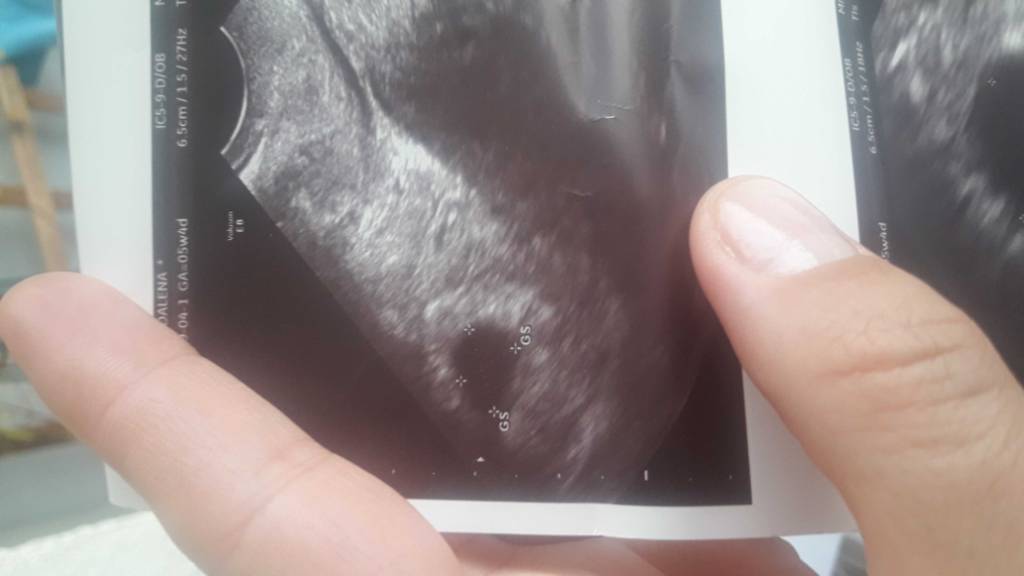

Liczony wg miesiączki 5 tydzień 4 dni.Super. A który to tydzień?

u mnie byl 5+4 i byl wodac peherzyk 8x13mm ale nie bylo jeszcze zarodka.a ktory tydz?

Myślę, że na następnej wizycie zobaczysz już więcej. Kiedy masz kolejny termin?u mnie byl 5+4 i byl wodac peherzyk 8x13mm ale nie bylo jeszcze zarodka.

Wyszłam od lekarza z uśmiechem na ustach jest pęcherzyk i ciałko żółte! Wierzę, że w tej ciąży będzie wszystko dobrzeTeraz 3 tygodnie zwolnienia do kolejnej wizyty.